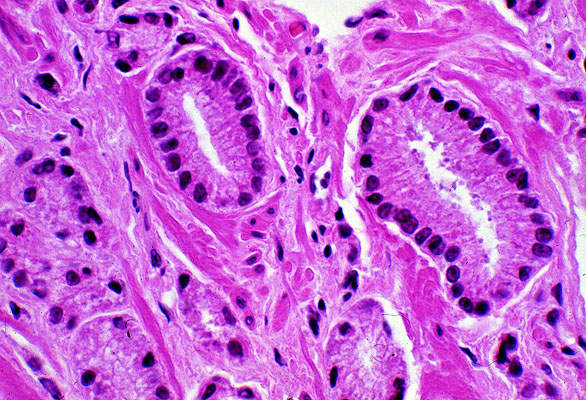

Carcinoma of the prostate, histology, high power

Here the structure of the neoplastic glands is seen to better advantage. Note that no myoepithelial cell layer can be seen near the basement membrane (compare to the slide of benign prostatic hypertrophy). Also, "back to back" gland formation, without intervening stroma, is seen best in the lower left hand corner of the photomicrograph.